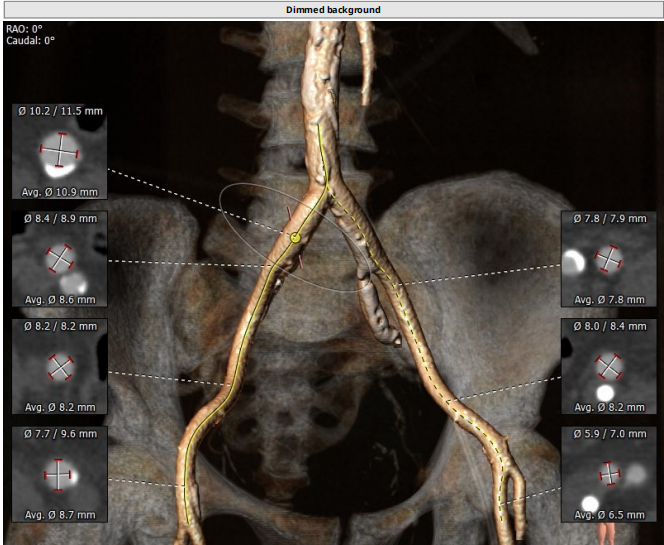

术前CT评估

路入分析:主动脉弓部、胸主动脉、腹主动脉可见多发钙化灶,操作需 谨慎,左颈动脉及左锁骨下动脉直径符合入路条件。

患者TYPE2型二叶瓣,左无、右无冠窦融合可能,左右部分粘连可能,轻度钙化,瓣叶增厚,法式窦结构不大,双冠高度可,升主动脉未见明显增宽,心脏角度不大,左室大,主动脉弓部走行较平缓,主动脉弓部、胸主动脉、腹主动脉可见多发钙化灶,操作需 谨慎。